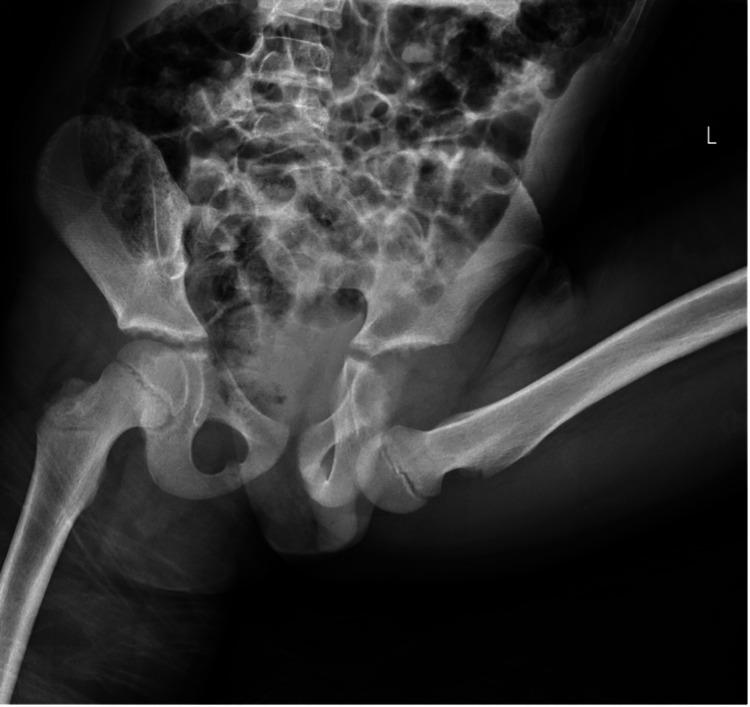

Merry-go-rounds are not as innocuous as they may seem. Pediatric hip anterior-inferior dislocations are very rare and can be associated with low-energy trauma. Prompt recognition of pediatric hip dislocations is vital, and this should be treated as a time-sensitive orthopedic emergency. Closed reduction within 6 hours minimizes the risk of avascular necrosis (AVN). We present a case of a 9-year-old boy with an inferior-anterior hip dislocation following low energy trauma while playing on a merry-go-round. The patient was emergently brought to the theatre for closed reduction under general anesthesia within 6 hours. At his 12-month follow-up, he has a full range of motion without any pain.

旋转木马并非看上去那么无害。小儿髋关节前下脱位非常罕见,可能与低能量创伤有关。及时识别小儿髋关节脱位至关重要,应将其视为时间紧迫的骨科急症。6小时内进行闭合复位可将缺血性坏死(AVN)的风险降至最低。我们报告一例9岁男孩在玩旋转木马时遭受低能量创伤后发生髋关节前下脱位的病例。该患者在6小时内被紧急送往手术室接受全身麻醉下的闭合复位。在他术后12个月的随访中,他的关节活动范围正常,没有任何疼痛。